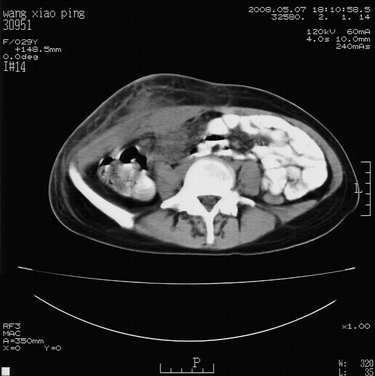

标题: CT13306:F,29,阑尾炎手术后20天,右下腹切口处包块. [打印本页]

标题: CT13306:F,29,阑尾炎手术后20天,右下腹切口处包块.

b超切口疝。

皮肤切口愈合良好。炎性肿块?

肿块密度较低,周围见有条索状影,边界不清,考虑为炎性病变可能大,必要是做增强看看。

支持阑尾术后切口感染。

切口处见液性密度影,周围肌肉肿胀,脂肪层密度增高。

符合术后并发症。